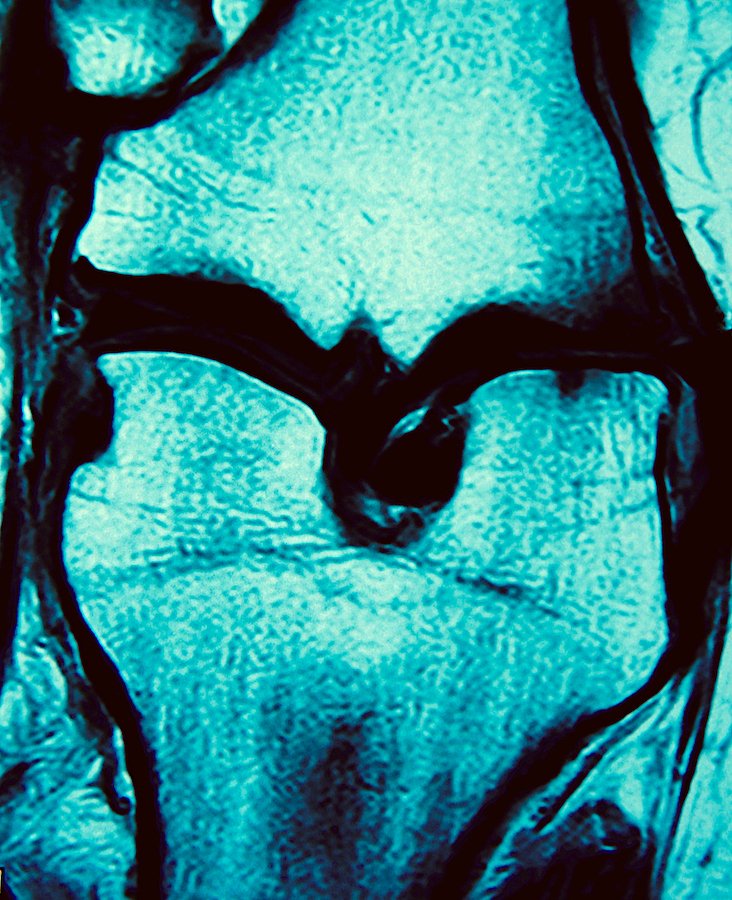

saturday night fever (boy meets girl diptych)

Selected for July/Aug 2022 exhibition in Art No.23’s Barcelona gallery.